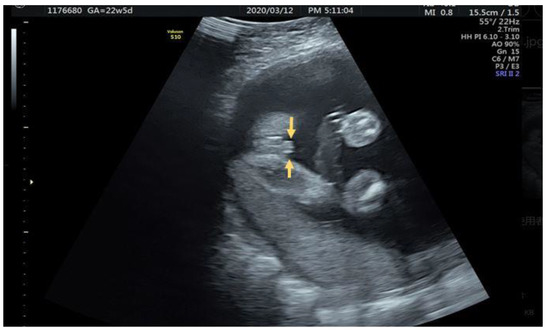

2.2. Case 2